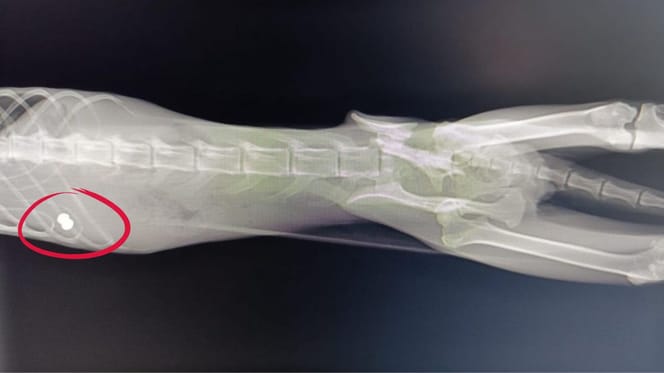

La radiografía de la gata desvela lo que hay en su cuerpo.

Durante la revisión de la gata, descubrieron algo que ni el propio veterinario podía creer: Sabrina tenía la cadera rota desde hacía al menos 20 días y, además, un perdigón alojado en su cuerpo, fruto de un disparo antiguo.

A pesar del dolor, Sabrina sigue viva. "El traumatólogo dice que lleva unas tres semanas con la cadera rota. Nadie sabe cómo ha podido resistir", explican desde la asociación en su perfil de Instagram.

Los veterinarios aseguran que la cadera de Sabrina ya se está soldando mal, incluso pinzándole el nervio. Si no intervienen pronto, no podrá hacer sus necesidades ni volver a caminar bien.